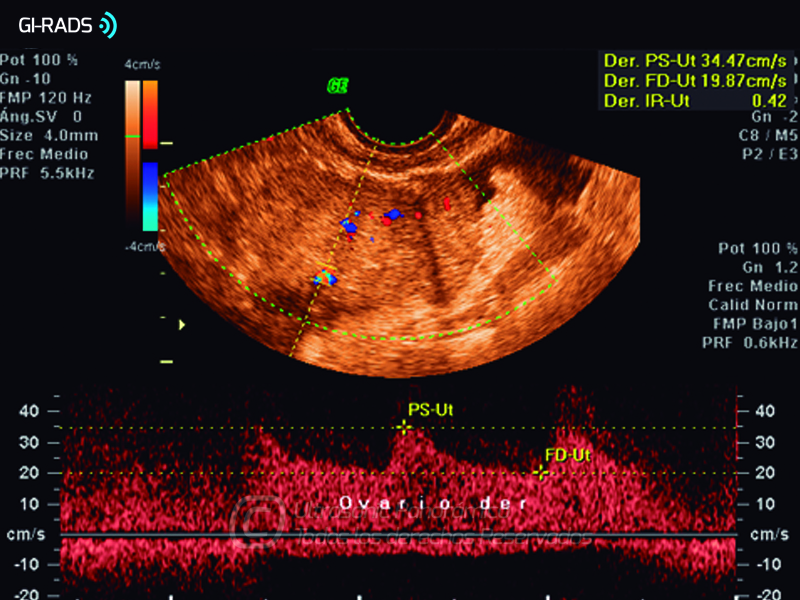

Cáncer Anexial – Baja Resistencia

• Cáncer Anexial – Baja Resistencia